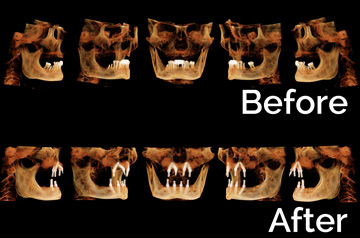

- Extractions with Alveoloplasty and Immediate Implants

- Temporary Denture Conversion into Temporary Bridge